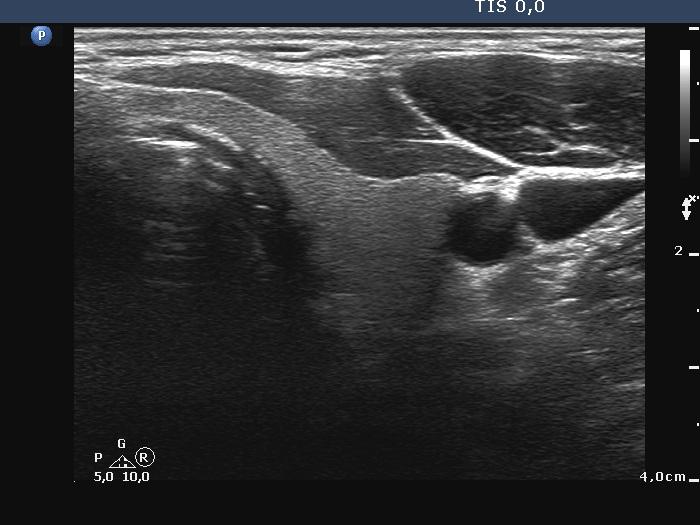

Palpation: A very firm node in the left supraclavicular region.

Ultrasonography. The thyroid was echonormal and intact. There was a large and several small lymph nodes in the left supraclavicularegion. The nodes did not have hilum, the largest one presented with irregular margins and irregular vascularity. The diameters of the node were 31x23x45 mm, width, depth, length, respectively.